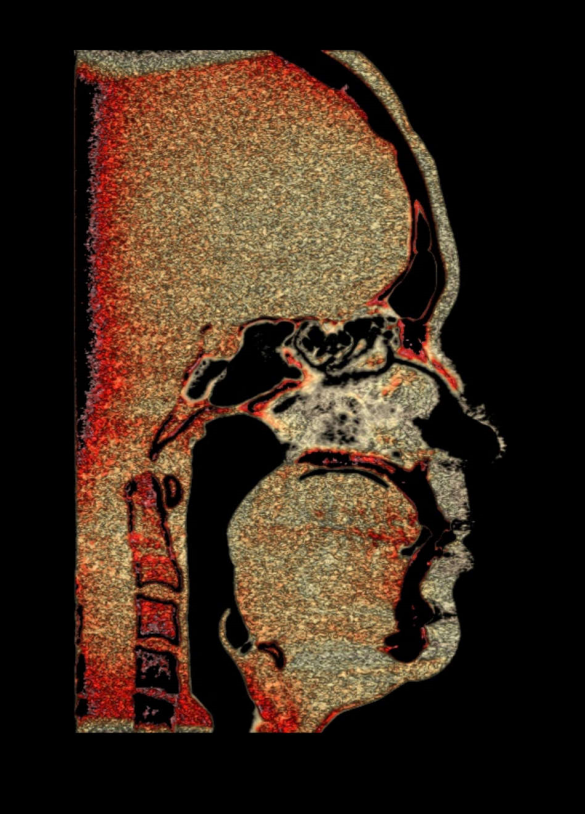

TC de face (do Hióide à Glabela), reconstrução 3D do tecido ósseo, radiografia panorâmica, telerradiografia lateral com traçado, cortes transversais e axial de maxila e mandíbula e arquivo DICOM- entregue em pasta de Pvc.

TC de face (do Hióide à Glabela), reconstrução 3D do tecido ósseo, radiografia panorâmica, telerradiografia lateral e frontal com traçado, cortes transversais e axial de maxila/mandíbula e arquivo DICOM – entregue em pasta de Pvc.

TC de face (do Hióide à Glabela), reconstruções 3D do tecido mole/ósseo/vias aéreas, radiografia panorâmica, telerradiografia lateral e frontal com traçado, cortes transversais e axial de maxila/mandíbula, ATM e arquivo DICOM – entregue em pasta e caixa de Pvc.